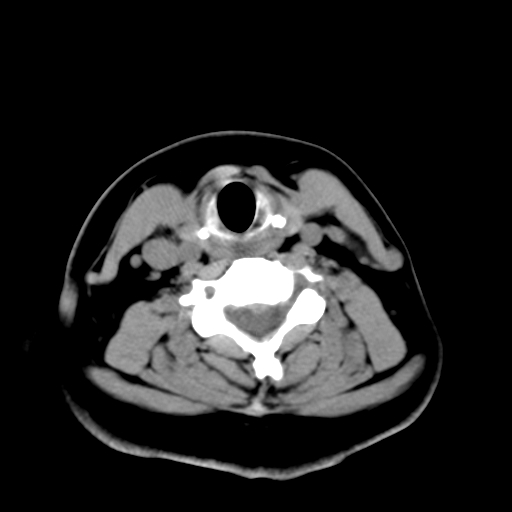

标题: CT25491:女,55岁,发现左侧甲状腺肿块一个月。 [打印本页]

标题: CT25491:女,55岁,发现左侧甲状腺肿块一个月。

女,55岁,发现左侧甲状腺肿块一个月,彩超示:甲状腺多发结节伴左叶结节液化。

考虑左侧甲状腺结节性甲状腺肿,不排除甲状腺腺瘤。